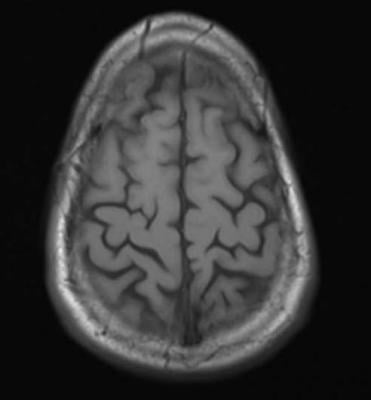

May 19, 2015 — New study results show a simple blood test to measure brain-specific proteins released after a person suffers a traumatic brain injury (TBI) can reliably predict both evidence of TBI on radiographic imaging and injury severity. The potential benefit of adding detection of glial fibrillary acidic protein breakdown products (GFAP-BDP) to clinical screening with computed tomography (CT) and magnetic resonance imaging (MRI) is described in an article published in Journal of Neurotrauma.

Paul McMahon of the University of Pittsburgh Medical Center, and a team of international researchers, including TRACK-TBI investigators, analyzed blood levels of GFAP-BDP from patients ages 16-93 years treated at multiple trauma centers for suspected TBI. They evaluated the ability of the blood-based biomarker to predict intracranial injury as compared to the findings on an admission CT and a delayed MRI scan. The authors reported a net benefit for the use of GFAP-BDP above imaging-based screening alone and a net reduction in unnecessary scans by 12-30 percent in the article "Measurement of the Glial Fibrillary Acidic Protein and Its Breakdown Products GFAP-BDP Biomarker for the Detection of Traumatic Brain Injury Compared to Computed Tomography and Magnetic Resonance Imaging.”